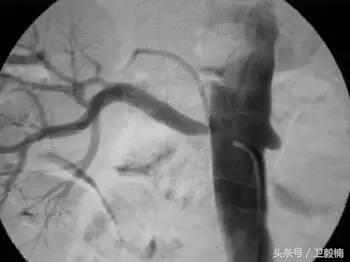

亦称介入性血管造影学(Interventional angiography),是指在诊断性血管造影的同时,自导管向血管管腔内注射药物或某些物质或施行某种措施,以达治疗目的。常用血管介入技术有三种。

2、经导管血管栓塞法(Transcatheter embolization)